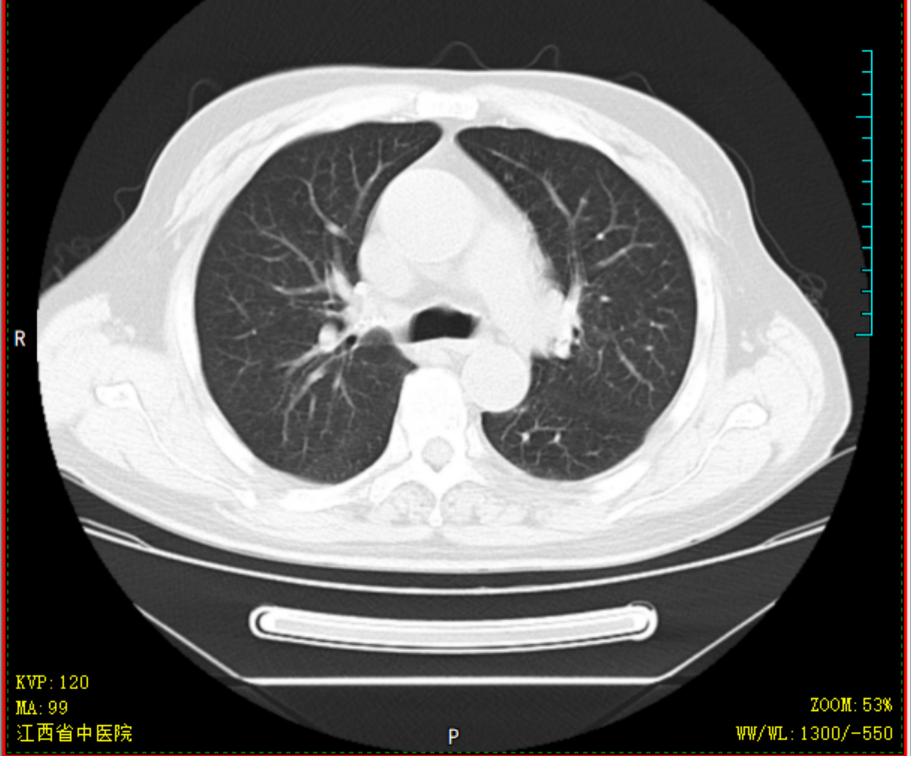

胡大爷,男,69岁,2020-4-14因“头晕乏力”就诊某省级医院,完善骨髓细胞学等检查后诊断为AML-M2a型,中危组;排出化疗禁忌症后,予标准DA方案化疗治疗,化疗过程中出现持续高热,热峰39.5℃,肺部感染、重症肺炎,恶心呕吐明显,予美罗培南+万古霉素抗感染,伏立康唑抗真菌感染,输注红细胞、血小板等治疗,化疗结束后复查骨髓细胞学示AML-NR骨髓象(急性髓系白血病未缓解骨髓象),经40天住院治疗病情平稳后出院,出院时体重减轻10kg。因为恐惧化学治疗,自行停化疗。2020-07-23患者因疲劳乏力加重就诊于我院,要求中医调理,入院查血常规示重度贫血、血小板减少,生化示肝功能不全、高尿酸;骨髓提示AML-NR骨髓象(急性髓系白血病未缓解骨髓象)。入院后予中药汤剂益气养血,并热敏灸温通经络。经治疗后患者乏力疲劳、贫血明显改善,排除治疗禁忌后,08-13起减低剂量化学治疗,同时口服我科经验方参芪杀白汤益气养血、扶正祛邪抗肿瘤,同时调理脏腑气机减少化疗不良反应,起增效减毒之功;热敏灸疗法灸肺腧穴固护肺卫之气预防外邪入侵,灸脾腧穴、肾腧穴固先后天之本促进气血化生。全程未出现呕心呕吐、骨髓抑制等常见不良反应,09-07骨髓细胞学示AML-CR骨髓象(急性髓系白血病完全缓解骨髓象)、白血病微小残留MRD提示阴性。2020-09-08返院行中西医结合方案抗白血病治疗,过程顺利,结束治疗后09-15出院 。经西医结合治疗不但是患者的症状改善明显,同时提高患者生活质量,同时保证了患者的临床疗效。